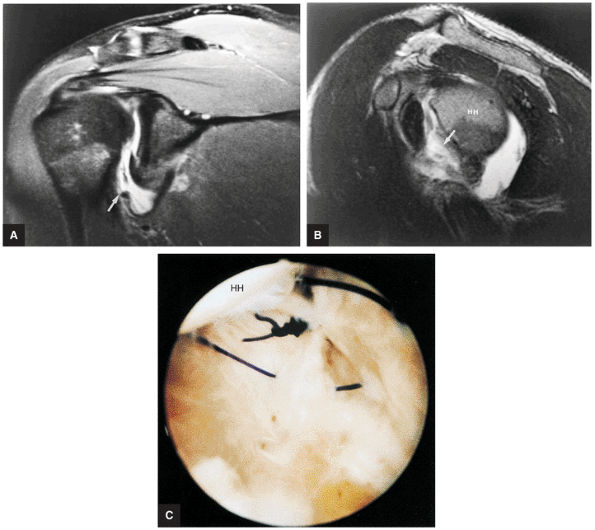

FIGURE 8.102 ● (A) The anterior undersurface of the acromion and the coracoacromial ligament form the coracoacromial arch. The subacromial subdeltoid bursa facilitates the passage of the rotator cuff and proximal humerus under the coracoacromial arch. (B) A superior axial image shows the anterior-to-posterior extent of the coracoacromial (CA) ligament perpendicular to the supraspinatus tendon. The fluid in the subacromial-subdeltoid bursa represents fluid between two serosal surfaces in contact with each other. One serosal surface is contributed by the undersurface of the coracoacromial arch and deltoid, and the other serosal surface is on the bursal side of the cuff.

|

![]() |

FIGURE 8.103 ● Pseudospur. The normal broad attachment of the coracoacromial ligament to the inferior surface of the acromion is shown on (A) T1-weighted coronal oblique and (B) sagittal oblique images. The low-signal-intensity acromial cortex (black arrows) and adjacent coracoacromial ligament and lateral slip of the deltoid attachment (white arrows) give the false impression of a small subacromial spur in the coronal plane. This pseudospur should not be misinterpreted as impingement; otherwise, unnecessary acromioplasties may be performed on patients with a normal coracoacromial ligament attachment and no associated acromial spurs.